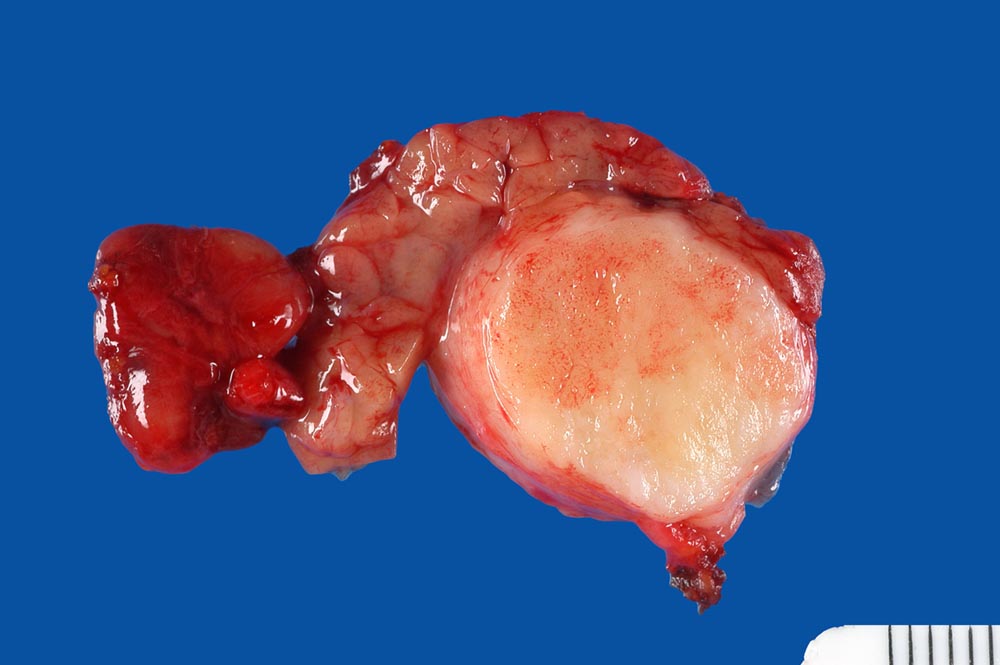

Makroskopie:

Makroskopisch sind pleomorphe Adenome scharf begrenzt. In den grossen Speicheldrüsen sind die meist solitär wachsenden Knoten von einer Kapsel umgeben, nicht aber in den kleinen Speicheldrüsen. Rezidivtumoren bilden oftmals multiple Knoten.

• Oben im Präparat dem Tumor kappenförmig aufsitzende seromuköse Speicheldrüse (Glandula submandibularis). Das sollte der Kliniker dem Pathologen mitteilen: